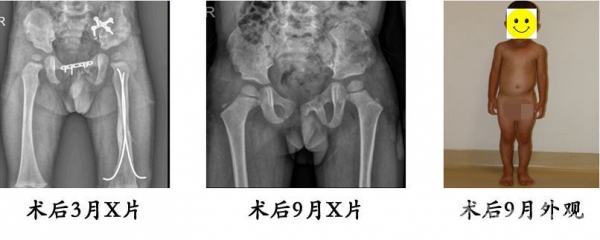

13.严某某,女,4岁,高处坠落伤(股骨颈、股骨干骨折),术后恢复颈干角、前倾角。